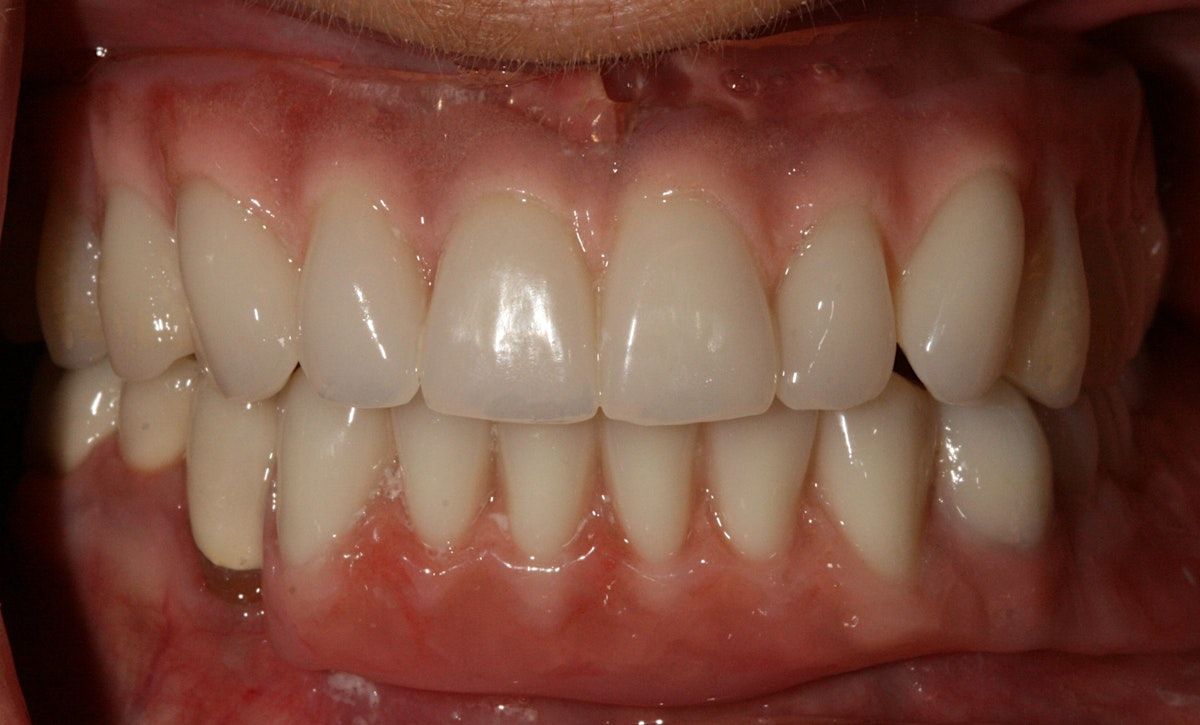

Topics that will be covered include: the principles of RPD design and philosophy, precision partial attachment systems, and implant incorporation into RPD design. 12 CE credits offered through the GDA (also applicable for those attending from out of state).